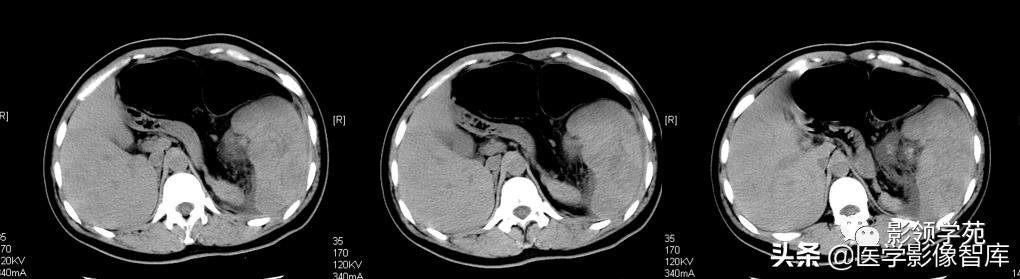

【CT表现】

1.CT平扫:1)脾内见圆形、类圆形低密度病灶,边界较清楚。2)较大血管瘤时,脾脏体积可增大,瘤体中央可有瘢痕形成,表现为更低密度,当内部有新鲜出血时,可见高密度区。3)病灶大小不等,多为单发,也可多发,可见有斑点状、星芒状钙化灶。

2.增强扫描:1)肿瘤边缘多呈斑片状强化,静脉期和平衡期强化扩大并逐渐向中心充填,延迟后与正常脾脏密度一致。与肝血管瘤呈类似改变。2)当肿瘤中心有血栓形成或瘢痕存在时,中心可有始终不强化区域。